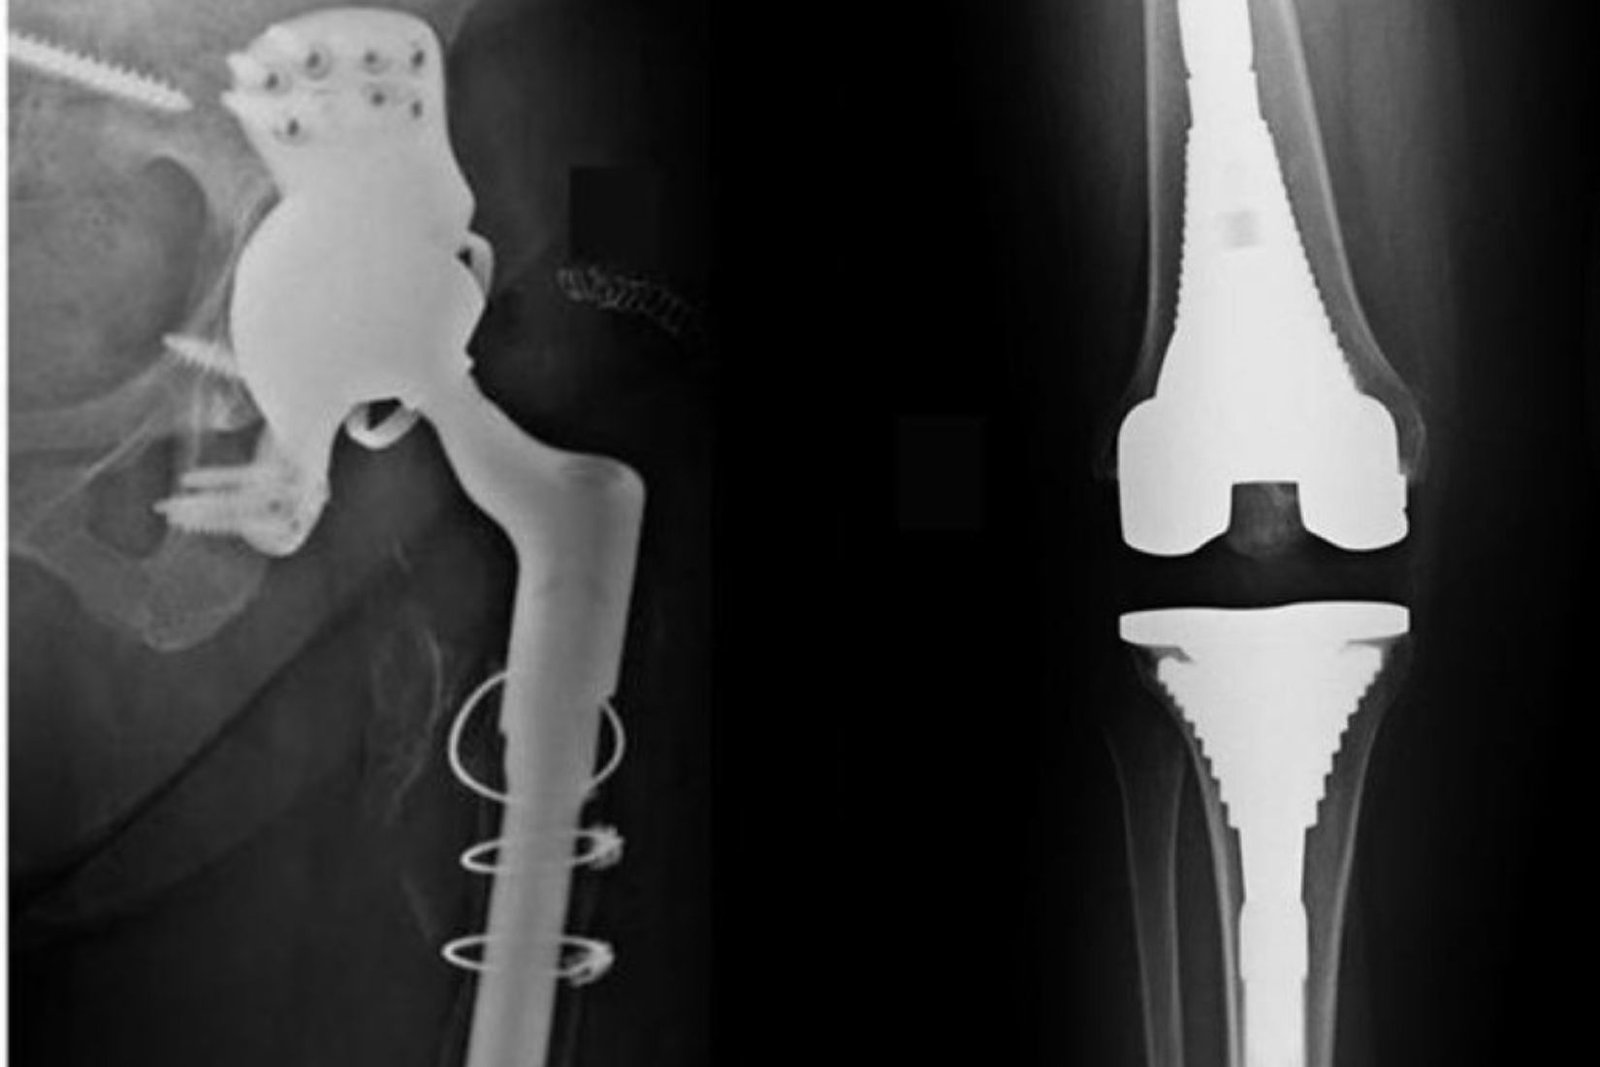

Total hip replacement surgery for degenerative hip disease, arthritis or trauma.

Total knee replacement for arthritis or deformity.

Complex revision surgeries for failed implants or infection.